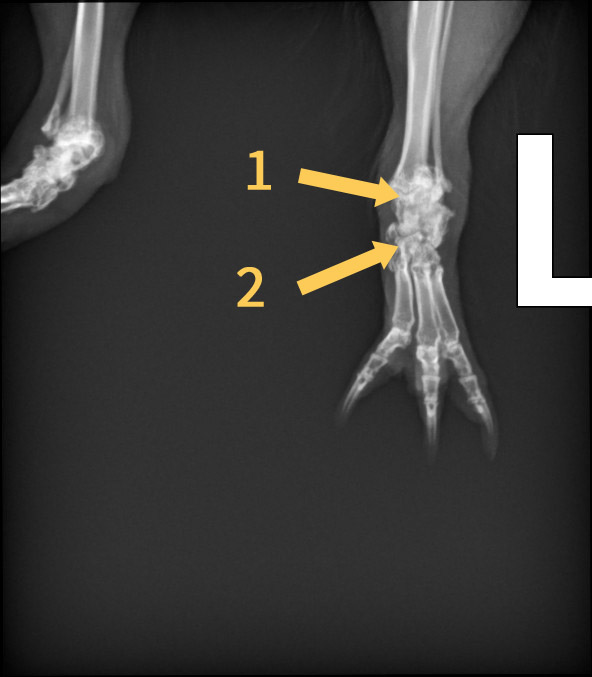

• Ich habe heute von Helga die Röntgenbilder bekommen. Zudem habe ich eine Physiotherapeutin gefunden. die sich an Schweinchen mal ausprobieren würde. Helga kommt mittlerweile mutig her und nimmt Futter gerne. Nur die Medis muss ich noch reinschmuggeln. Sie läuft auch deutlich besser und mehr. Ihr Schilddrüsenwert war tatsächlich mit 0,9 unter dem Grenzwert von 1,1 (Ich weiß die Einheit leider nicht). Da das ja alles nicht so eindeutig ist fordert die Tierärztin nochmal einen Wert nach und wir kontrollieren in 4-6 Wochen und stellen sie dann bei Bedarf ein.

Die Röntgenaufnahmen würde ich gerne besser verstehen:

Auf der zweitletzten Aufnahme ist das Sprungelenk m.E. klar als das zu sehen, was bei uns Menschen im Bereich der Ferse wäre. Etwas weiter links davon das dunklere ist dann vermutlich der Mittelfußknochen?

Du hattest geschrieben, dass Ihr Sprunggelenk stark geschädigt ist. Aber sieht es auf dem letzten Bild nicht so aus, als sei auch der Mittelfußknochen kaputt?

• Ich habe in den Bildern 1 und 2 markiert. Dabei vermute ich, dass 1 das Sprungelenk ist und 2 der Mittelfußknochen. Falls das richtig sein sollte, sieht der doch auf dem 2. Bild auch nicht normal aus?

Wie gesagt, ich verstehe kaum etwas davon und kann falsch liegen. Mach Dir daher bitte keine unnötigen Sorgen.

Den hatte ich glatt übersehen. Ich könnte mir vorstellen, dass die Ärztin mit Sprunggelenk den Teil eingeschlossen hat, da der gesamte Bereich falsch ausgebildet ist. Weißt du, was ich meine? Ich habe leider gerade unsere anderen Röntgenbilder von Füßchen nicht zur Hand um das zu vergleichen.